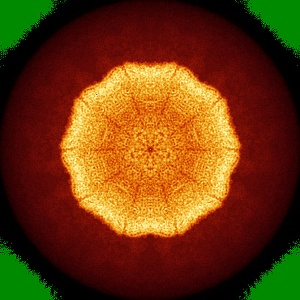

The cryo-EM structure of HAV bound to a neutralizing antibody-F4

Structural basis for neutralization of hepatitis A virus informs a rational design of highly potent inhibitors.

Cao L , Liu P , Yang P , Gao Q, Li H, Sun Y , Zhu L, Lin J, Su D, Rao Z, Wang X

(2019) PLoS Biol , 17 , e3000229 - e3000229